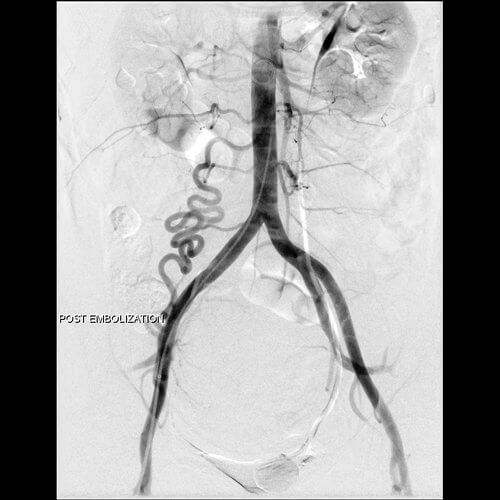

42 year old female who presents with abnormal bleeding, menstrual cramping, and frequent urination and subsequently undergoes UFE.

42 year old female who presents with abnormal bleeding, menstrual cramping, and frequent urination and subsequently undergoes UFE.